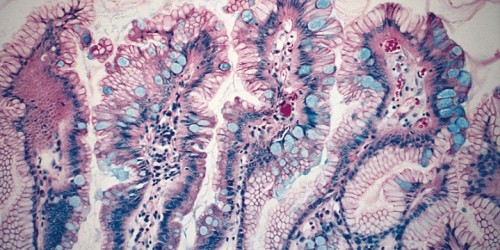

Furthermore, if biopsy establishes that the standard lining cells of the esophagus are substituted by intestinal type lining cells, it is the second sign that Barrett’s esophagus actually occurred. These abnormal cells include goblet cells that produce mucus and many other kinds of cells, even the cells that resemble those cells of the lining of the stomach. Nevertheless, the intestinal goblet cells must be present when Barrett’s esophagus occurs. If the biopsy establishes that there are no goblet cells, then Barrett’s esophagus should not be diagnosed.